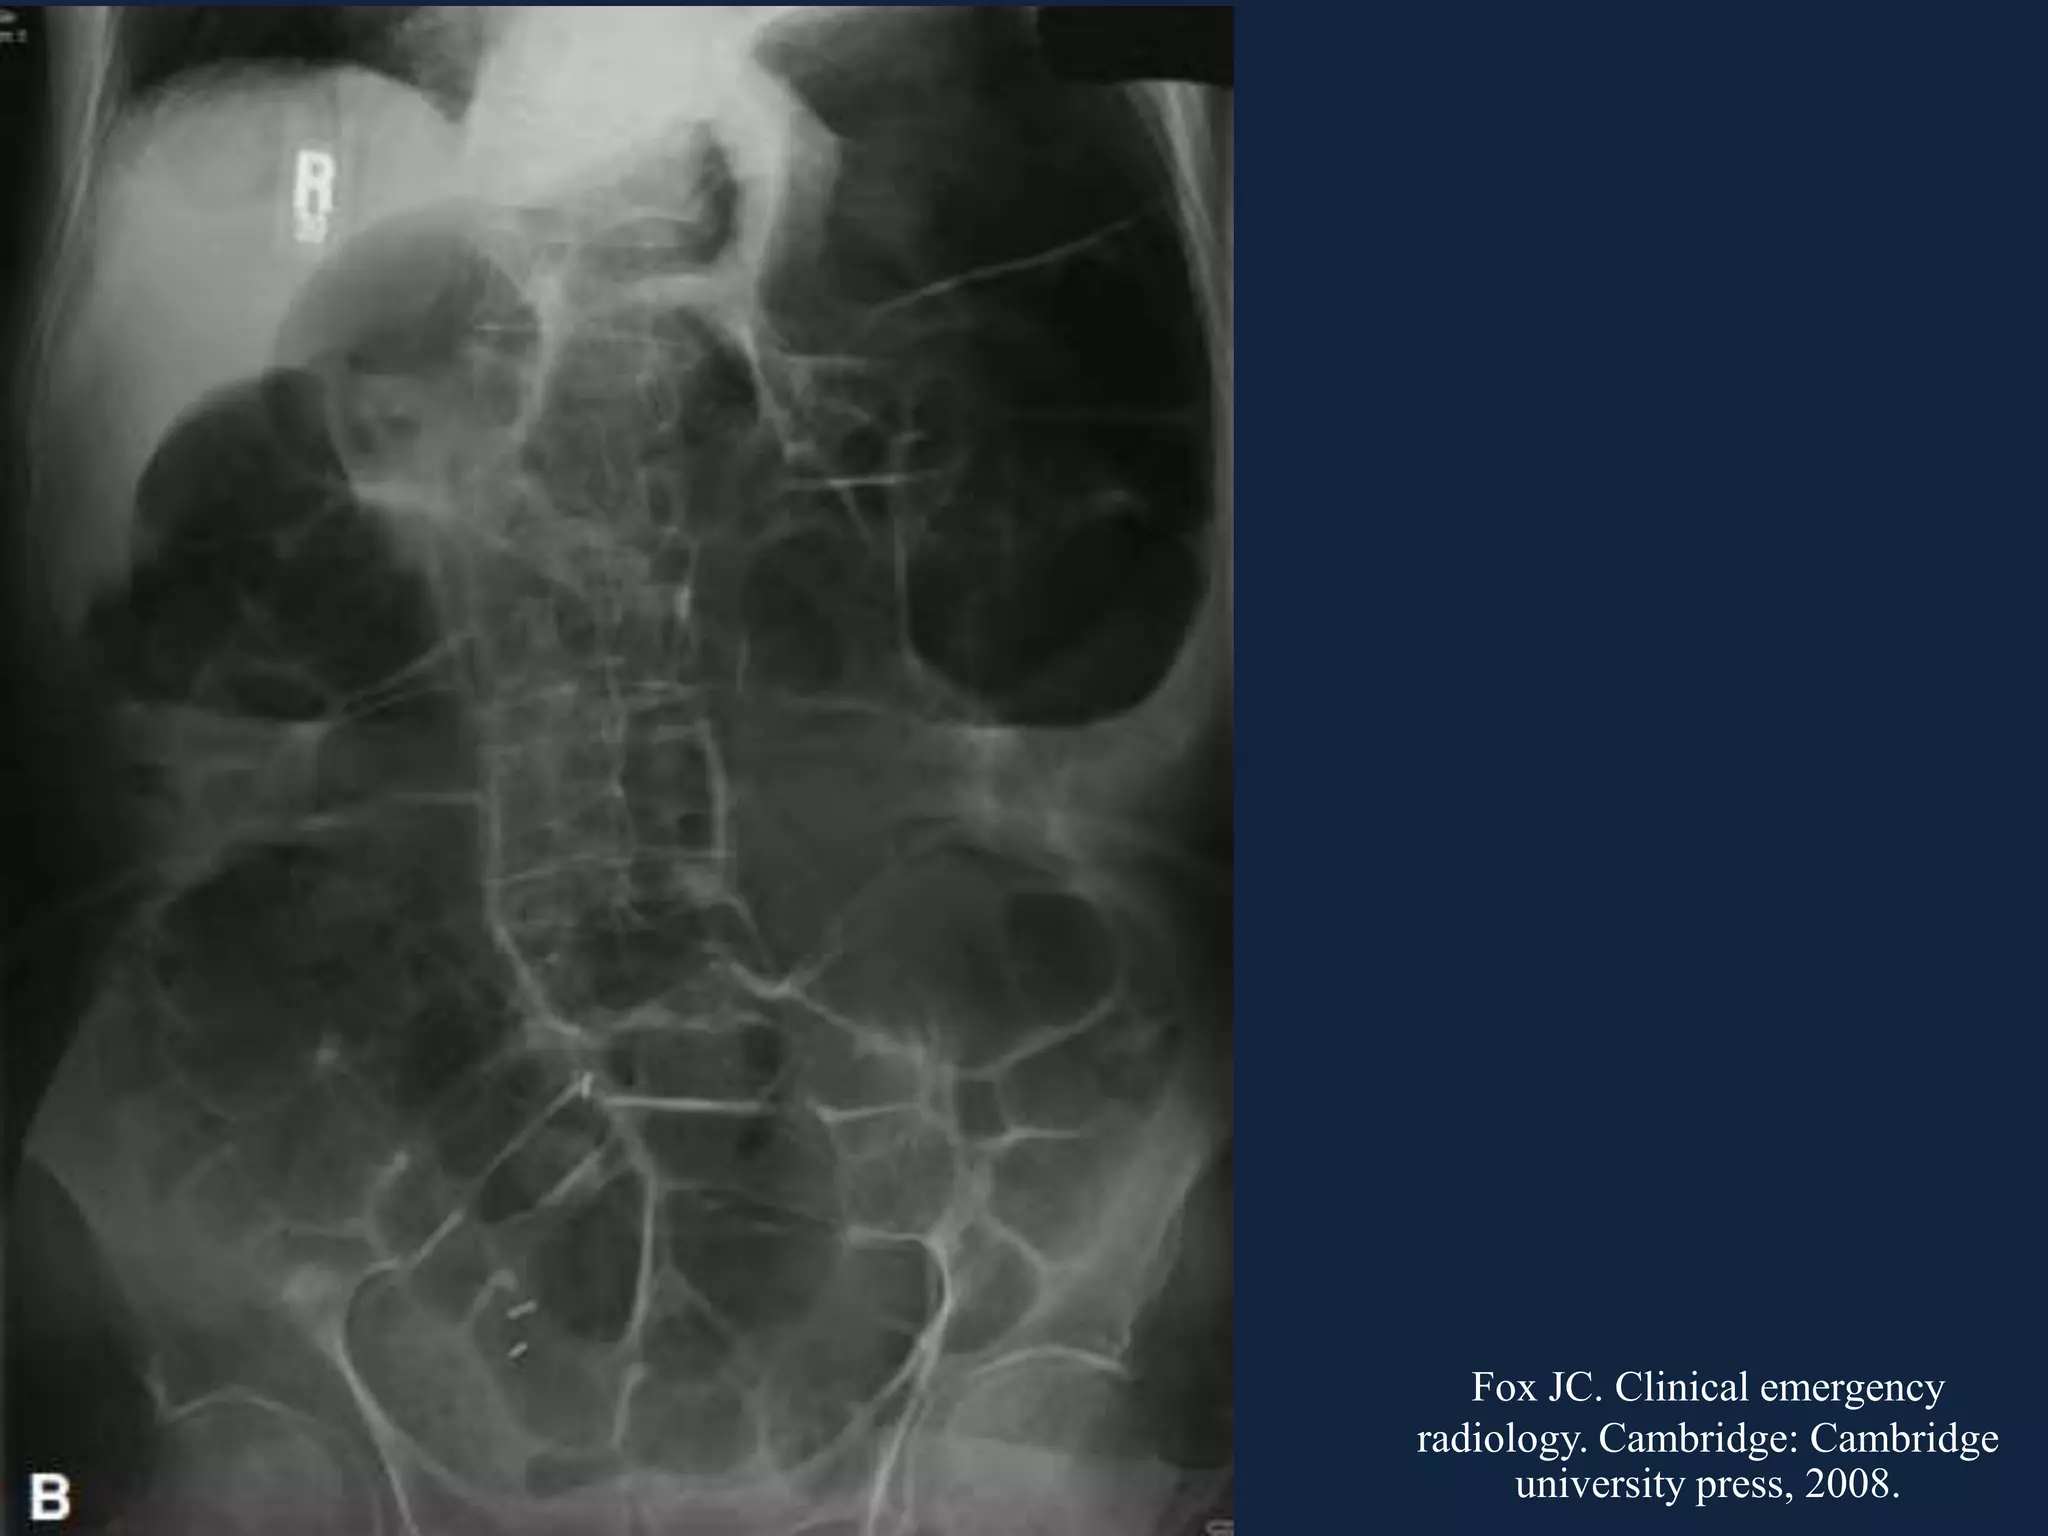

• #10 Cecal valvulus = cecum ที่เป็น reverse C

• #11 Ascending colon dilatation No air in rectum Present of small bowel dilation (IC valve incompetent)